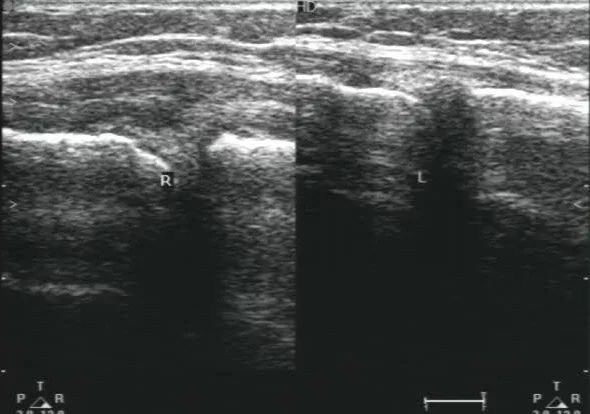

44岁女性患者,右膝关节疼痛,放射检查未见骨关节异常,后来经过肌骨超声检查提示考虑右侧膝关节内侧副韧带挫伤,肌骨超声看到你不知道的肌肉损伤。